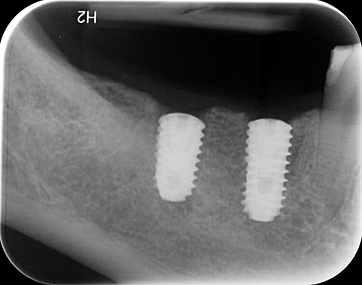

Two implants placed using the X-Guide System by Dr Ashish Gulati at iDD. The results are excellent.